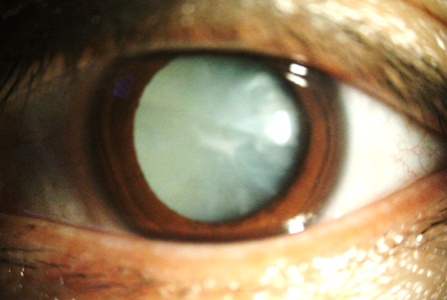

백내장은 약물이나 생활 습관의 변화로 되돌릴 수 없기 때문에 시력 장애가 일상생활에 방해가 되는 경우 수술이 유일한 치료법입니다. 백내장 수술은 흐려진 수정체를 제거하고 인공 안구 내 수정체(IOL)로 교체하는 것을 포함합니다. 이 시술은 침습적이라서 부담스럽지만 대부분의 환자가 며칠 이내에 시력이 크게 개선되기 때문에 많이 선택됩니다. 백내장 초기 단계에 있는 환자들은 특정 생활 습관을 조정하면 백내장의 진행이 지연될 수 있습니다. 선글라스를 착용하여 유해한 자외선으로부터 눈을 보호하고 항산화제가 풍부한 건강한 식단을 유지하며 금연하는 것이 백내장 예방에 도움이 됩니다. 정기적인 안과 검사는 눈 건강을 모니터링하고 백내장을 조기에 발견하는 데도 필수적입니다. 백내장 예방이 항상 가능한 것은 아니지만, 이러한 단계는 전반적인 눈 건강을 돕고 백내장 발병에 기여할 수 있는 당뇨병이나 고혈압과 같은 다른 질환으로 인한 합병증 위험을 줄일 수 있습니다.